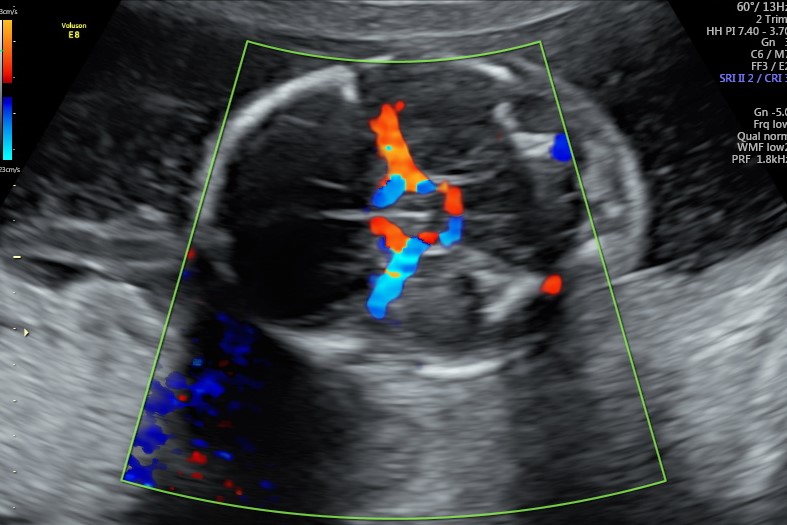

Non solo il tesoro è oggetto di valutazione, ma in questa ecografia lo è anche la mamma. Infatti, per vedere se siamo dei buoni incubatori, è importante la valutazione della resistenza delle arterie uterine.

La placenta, organo semplice strutturalmente ma dotato di una incredibile intelligenza biologica, modifica queste arterie rendendole dei vasi a bassa resistenza, assicurandosi, di conseguenza, un buon apporto di sangue per le fasi successive della gravidanza e in ultima analisi un corretto sviluppo fetale.